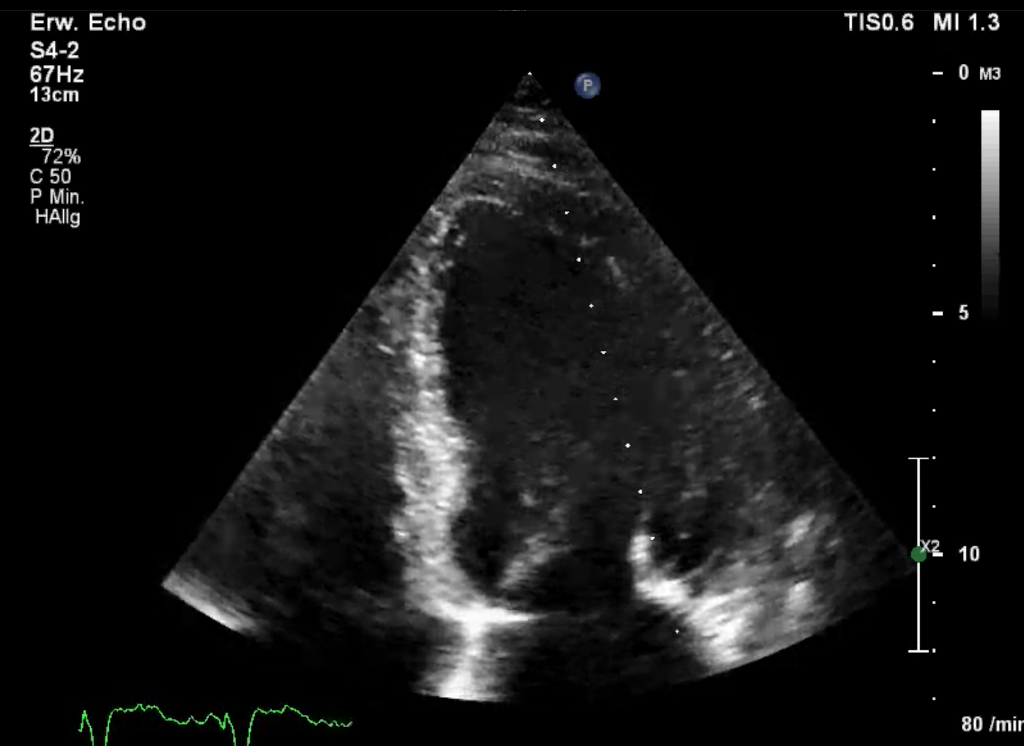

2D-Bild

2D-Bild (realtime)